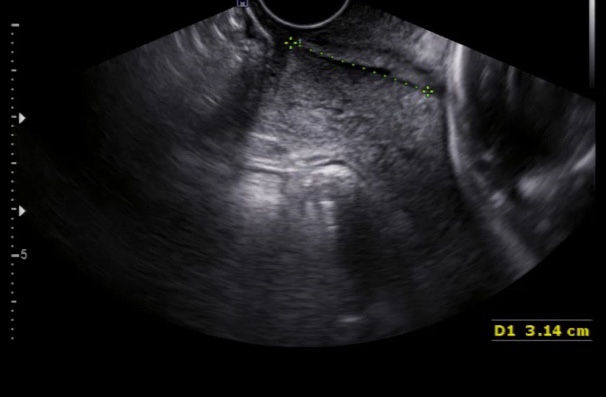

[24주] 예???? 수술이라뇽?.? _예방맥수술

저는 16주때부터 경부길이가 간당간당하게 3.6cm ~ 3.3cm를 왔다갔다 했어요 긴편은 아니지만 당시에는 벌...